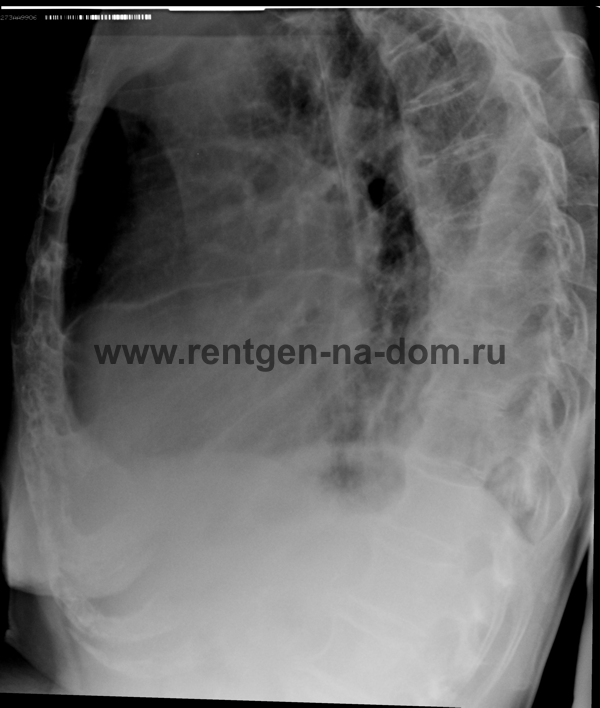

Пневмония – простыми словами воспаление легких – острое воспаление легочной ткани инфекционного происхождения с преимущественным поражением альвеол и интерстициальной ткани легкого. При этом жидкость скапливается в просвете альвеол, что ведет к уменьшению дыхательной поверхности легких. Пневмония может быть самостоятельным заболеванием или быть осложнением другого. Заподозрить пневмонию можно при аускультации (выслушивании) легких при дыхании. Поздняя диагностика и задержка с началом антибактериальной терапии ухудшают прогноз заболевания, возможен летальный исход. Поэтому при малейших подозрениях необходимо сделать рентген легких, особенно пожилым пациентам, а при подтверждении диагноза – поставить вопрос об экстренной госпитализации. Пневмония может лечиться и дома, но такое решение может принять только врач, основываясь на оценке состояния больного, рентгенологической картины легкого и анализов крови. Лечение пневмонии в большинстве случаев требует внутривенного введения антибиотиков, инфузионной терапии (капельниц) и других препаратов. Пациенты, обратившиеся в медицинский центр «Ваше Здоровье», смогут получить весь комплекс необходимых лечебно-диагностических мероприятий, в т.ч. рентген на дому.

Второй наиболее частой причиной, по которой выполняется рентген грудной клетки, является травма груди с подозрением на перелом рёбер. Может показаться, что ушиб грудной клетки является несерьезным основанием, чтобы обратиться к врачу и сделать рентген. Однако приглушая боль приёмом обезболивающих препаратов, можно пропустить ряд опасных осложнений. Сломанные рёбра могут ранить легкое и вызвать пневмоторакс, т.е. скопление воздуха, или гемопневмоторакс, т.е. скопление крови и воздуха в грудной полости. Перелом трех и более рёбер может вызвать серьёзные дыхательные нарушения, что особенно опасно у пожилых пациентов. Поэтому не стоит рисковать здоровьем и необходимо сразу обратиться к врачу. Пациенты, обратившиеся в наш медицинский центр "Ваше Здоровье", смогут получить весь комплекс необходимых лечебно-диагностических мероприятий, в т.ч. рентген на дому.

Получение качественных рентгеновских снимков на дому предъявляет серьёзные требования к рентгеновской аппаратуре. Далеко не каждый переносной рентгенаппарат позволяет получать снимки необходимого качества, чтобы достоверно поставить диагноз. Используемый нами рентгенаппарат АРА 110/160 в комплексе с компьютерным радиографом позволяет получать цифровые рентгеновские снимки высокого качества у пациентов различной комплекции и является уникальной услугой в Санкт-Петербурге, предоставляемой на дому.